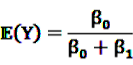

and  be random variables to describe the occurrence of drug exposure i and ADR j, respectively. The a priori expectations of X and Y are obtained as:

be random variables to describe the occurrence of drug exposure i and ADR j, respectively. The a priori expectations of X and Y are obtained as: and